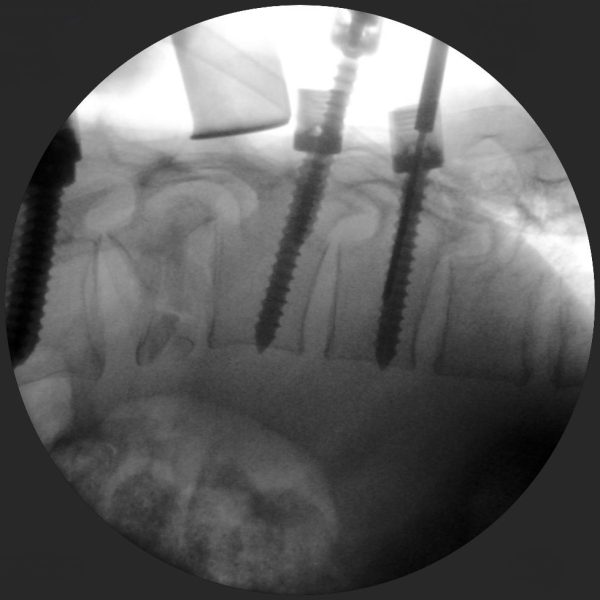

High-quality imaging

Skan-C uses advanced imaging technology, such as pulsed fluoroscopy and digital subtraction angiography, to provide highly detailed images of the affected area. This allows doctors to perform procedures with increased precision and accuracy, and better patient outcome

Clinical Evidence

Skan-C is a great C-arm for neurology treatments for several reasons